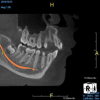

(4.) In a CBCT image axial view, the MB1 and MB2 canals are readily visible in tooth No. 14, and in the coronal view, these two separate canals can be seen to merge into a single apical opening.

Figure 4

Being able to see the number and shape of the canals accurately prior to treatment is the desire of any clinician who performs endodontics. Research suggests that, due to improved diagnostic accuracy, the final treatment plan may change in up to 50% of endodontic cases if CBCT is used rather than traditional 2D imaging.14,15 The question of whether or not a patient has an MB2 canal can be answered prior to opening the access preparation (Figure 4 and Figure 5). Visualizing single canals that bifurcate in the apical or middle third of the root or those that merge to a single apical opening can help clinicians to understand their instrumentation needs in advance. In addition, the ability to measure the length and shape of a canal planned for instrumentation prior to utilizing an apex locator helps to confirm any measurements obtained by other means. It should also be noted that the ability to see a pathosis in 3 dimensions and to involve the patient in understanding his or her condition prior to any decision-making allows for definitive treatment planning. In fact, many patients have pathoses associated with teeth that are asymptomatic that remain unknown to them until they are visually presented with the evidence (Figure 6).